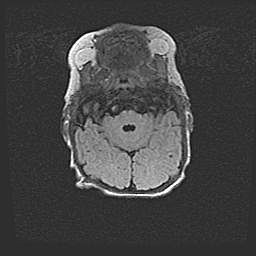

Церебральная ишемия II.

Возраст: 5 дней

Вес: 3400 г

Пол: женский

Окружность головы: 35 см

Срок гестации: 39 недель

Церебральная ишемия – это заболевание, характеризующееся недостаточностью (гипоксией) либо полным прекращением (аноксией) снабжения мозга кислородом по причине закупорки одного или нескольких сосудов. Это приводит к  что метаболическим расстройствам различной степени тяжести в тканях головного мозга, развитию коагуляционных некрозов и гибели нейронов.